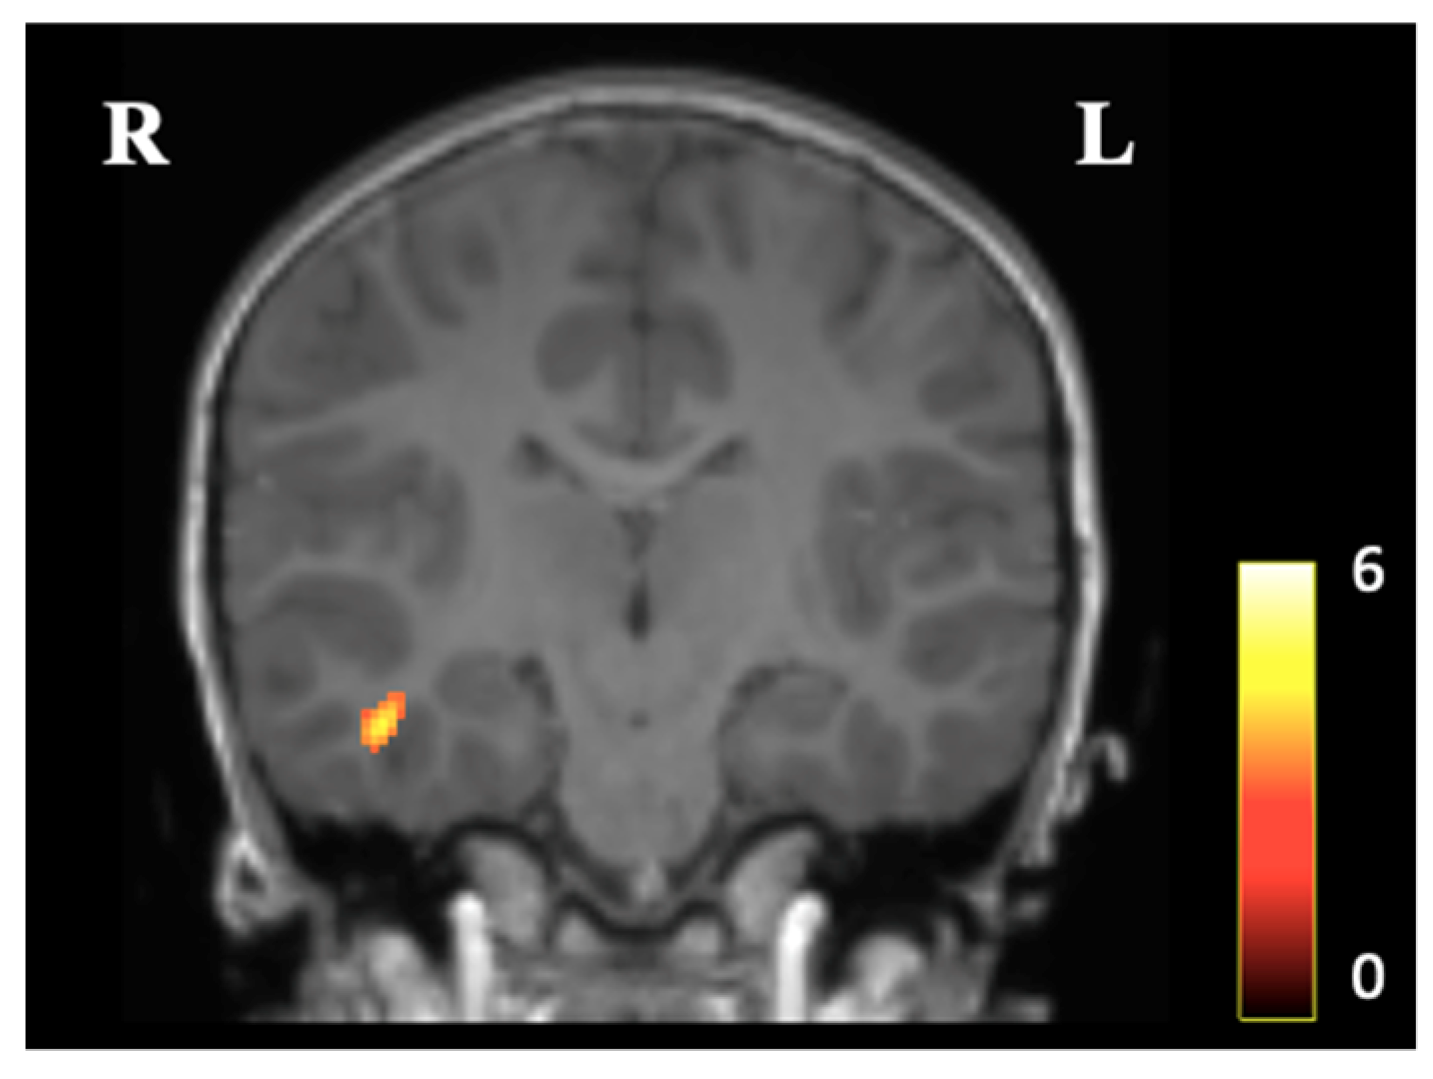

3.2. Voxel-Based Morphometry